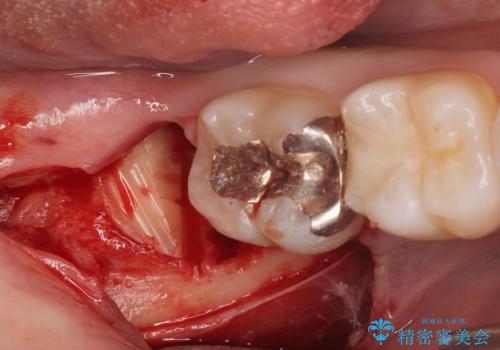

- 親知らずが痛くて抜きたいと来院。

CTを撮影し、神経の位置など確認し安全なことを確認して抜歯を行いました。

抜歯は当日行う事が出来ます。